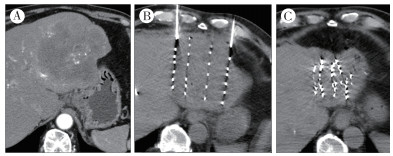

2.1 影像学疗效评估17例患者均行腹部增强CT扫描,利用mRECIST评价标准进行肿瘤大小的评估发现,粒子植入术后6个月总有效率最高,术后9个月病灶CR率(58.8%)最高,后呈逐渐下降趋势(表 1),典型病例见图 1;其中9例同时行MRI检查,观察T2W1和DWI信号变化情况,术后6个月病灶T2W1及DWI信号降低最明显(表 2)。

| 注 A:多次TACE术后及RFA术后效果不佳;B:术中植入粒子后;C:治疗后复查肿瘤基本灭活 图 1 1例68岁男性原发性肝癌患者粒子植入术前和术后效果比较 Fig.1 Comparison of results before and after postoperative effects of seed implantation in a 68-year-old male patient with primary liver cancer |